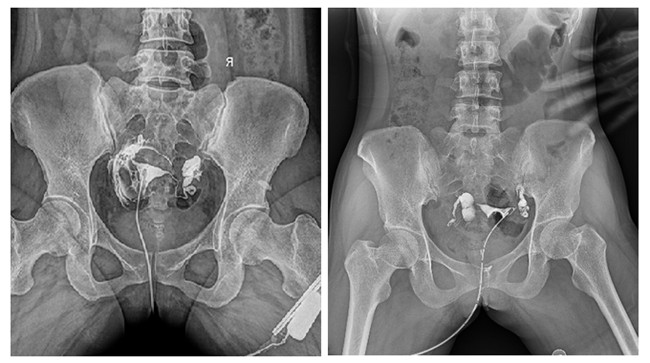

輸卵管造影檢查可根據造影劑在輸卵管及盆腔內的顯影情況了解輸卵管是否通暢、阻塞部位及宮腔形態,是超聲、CT、核磁、宮腔鏡、腹腔鏡、輸卵管鏡等所無法替代的。作為目前普放領域先進的影像設備,平板動態DR進行子宮輸卵管造影檢查,大大超越了過去的檢查技術,更加精準、便捷、高效。

相較于傳統胃腸機,動態DR矩形采集面積大,一次曝光即可顯示整個盆腔,大幅減少觀察時間,可控的瞬時照射避免受檢者吸收過多的X線,對育齡期女性的檢查尤為重要。毫秒級時間內高清點片,可以在造影劑流動的過程中完成拍片,抓拍到關鍵圖像,更加清楚地了解到管腔的具體通暢情況及堵塞部位,對檢查及診斷有非常重要的價值。

此外,應用平板動態DR進行子宮輸卵管造影,還可以在加壓推注下,使部分輸卵管輕、中度堵塞的患者得以通暢,起到一定的治療作用。